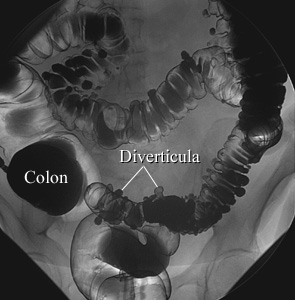

Air-Contrast Barium Enema

Diverticulosis

In an air-contrast study, the colon is first filled with barium and then the barium is drained, leaving only a thin layer of barium on the wall of the colon. The colon is then filled with air. This barium enema image shows pouches (called diverticula) in the wall of the colon.